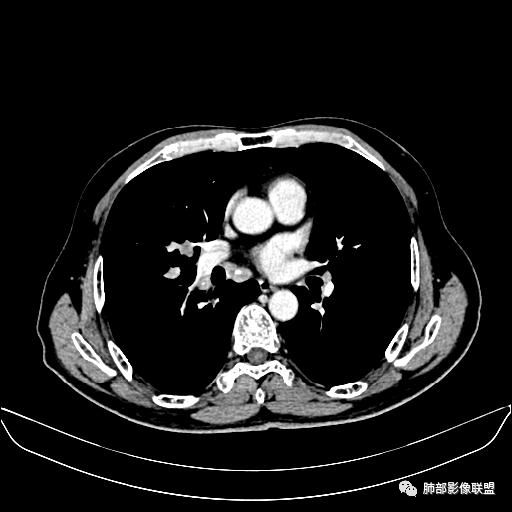

入院CT